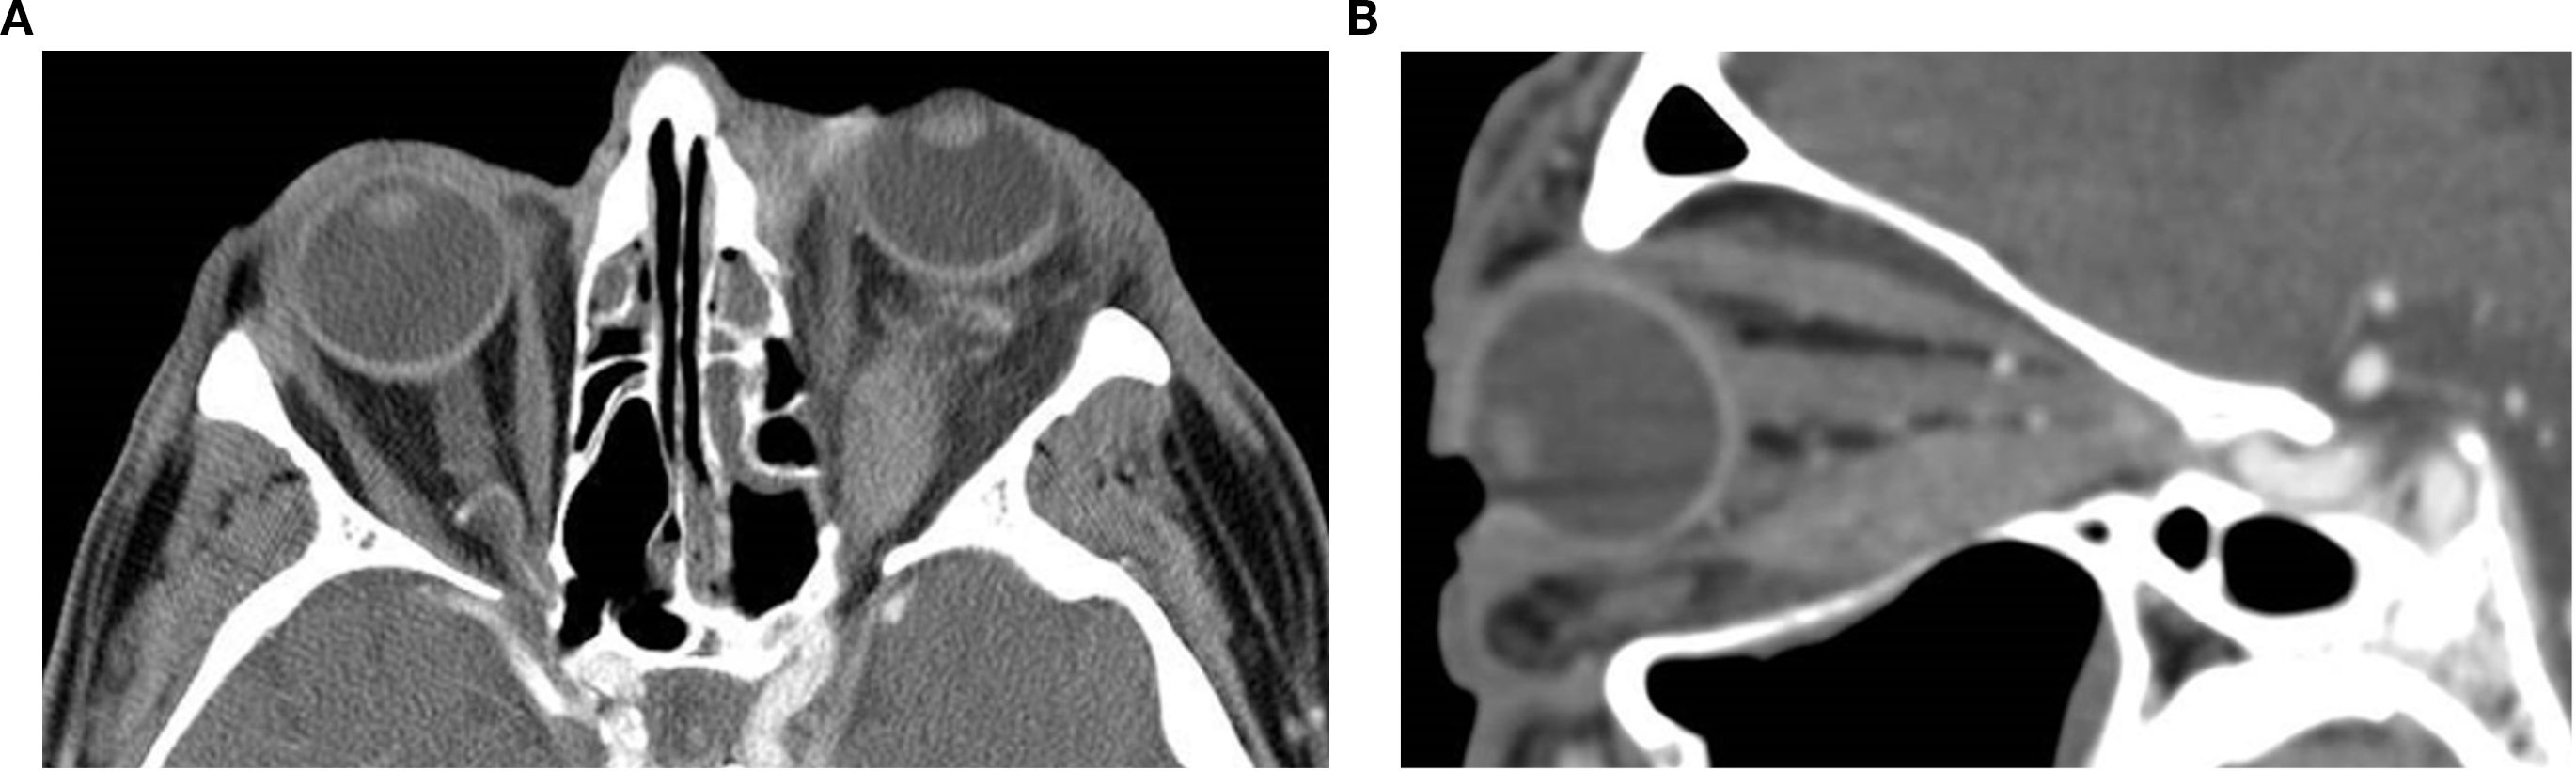

Orbital masses include a diverse spectrum of benign, malignant, inflammatory, and vascular lesions in pediatric and adult patients. Accurately diagnosing the type of lesion is critical, as management strategies differ significantly. Advanced imaging is therefore essential, and computed tomography (CT) is central to orbital evaluation. We reviewed the literature to synthesize evidence on CT features across common orbital pathologies and correlated imaging with clinical presentation to emphasize diagnostic relevance. CT characteristics are summarized for vascular lesions (cavernous venous malformation, lymphatic malformation), inflammatory conditions (orbital myositis, dacryoadenitis), benign lesions (dermoid cyst, pleomorphic adenoma), and malignant lesions (lacrimal gland lymphoma, adenoid cystic carcinoma, rhabdomyosarcoma). We present characteristic patterns of location, morphology, enhancement, and bone change, with practical discriminators and common pitfalls to aid differentiation. When used alongside clinical context, CT remains a preferred modality in many clinical settings due to its rapid acquisition, wide availability, and reliable depiction of bone and calcifications. It supports accurate diagnosis and informed management decisions in time-critical settings. This review provides a structured reference for interpreting CT findings across a wide range of orbital disease.